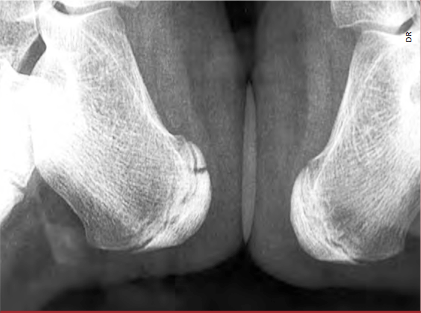

Fracture de l’extrémité inférieure du noyau d’ossification calcanéen gauche.